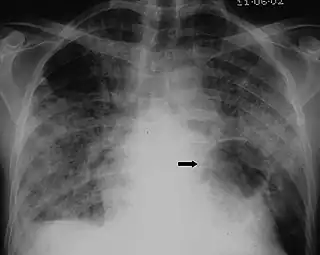

X-ray of a cyst in pneumocystis pneumonia[6]